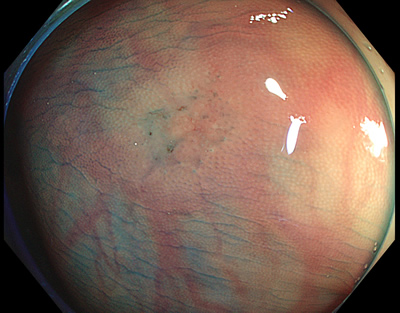

陥凹型過形成ポリープの完全切除

陥凹型腺腫はポピュラーなポリープです

一方、陥凹型過形成ポリープは、頻度が非常に低く、謎に包まれた病変で良く解っていません。

重要なことは、この病変は憩室や炎症、あるいは正常な腸の皺と非常に紛らわしく医師が意識しないと簡単に見逃すという事です。

気を付けて観察すると「実は稀ではない」病変なのです